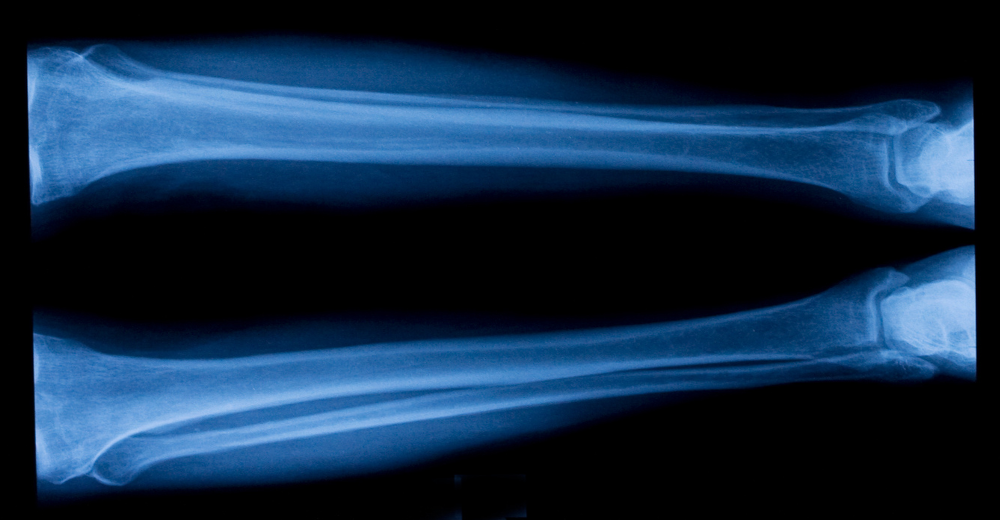

Il termine “RX” è l’abbreviazione di radiografia, un metodo diagnostico che utilizza i raggi X per ottenere immagini dettagliate delle strutture interne del corpo. Il termine “Tibio-Tarsica”, invece, si riferisce all’articolazione tra la tibia e le ossa del tarso del piede, che costituisce la base di supporto della caviglia. L’RX Tibio-Tarsica permette di analizzare in profondità le ossa e le articolazioni di quest’area, fornendo un quadro chiaro e completo per la diagnosi delle principali patologie che possono colpirla.

L’RX Tibio-Tarsica è una radiografia mirata all’esame delle ossa e delle articolazioni del piede e della caviglia. Questo esame sfrutta i raggi X per catturare immagini ad alta risoluzione, che mostrano eventuali anomalie come fratture, distorsioni o patologie degenerative. Grazie alla sua precisione, l’RX Tibio-Tarsica rappresenta uno degli strumenti più utilizzati per identificare problemi muscoloscheletrici e alterazioni strutturali in questa zona del corpo.